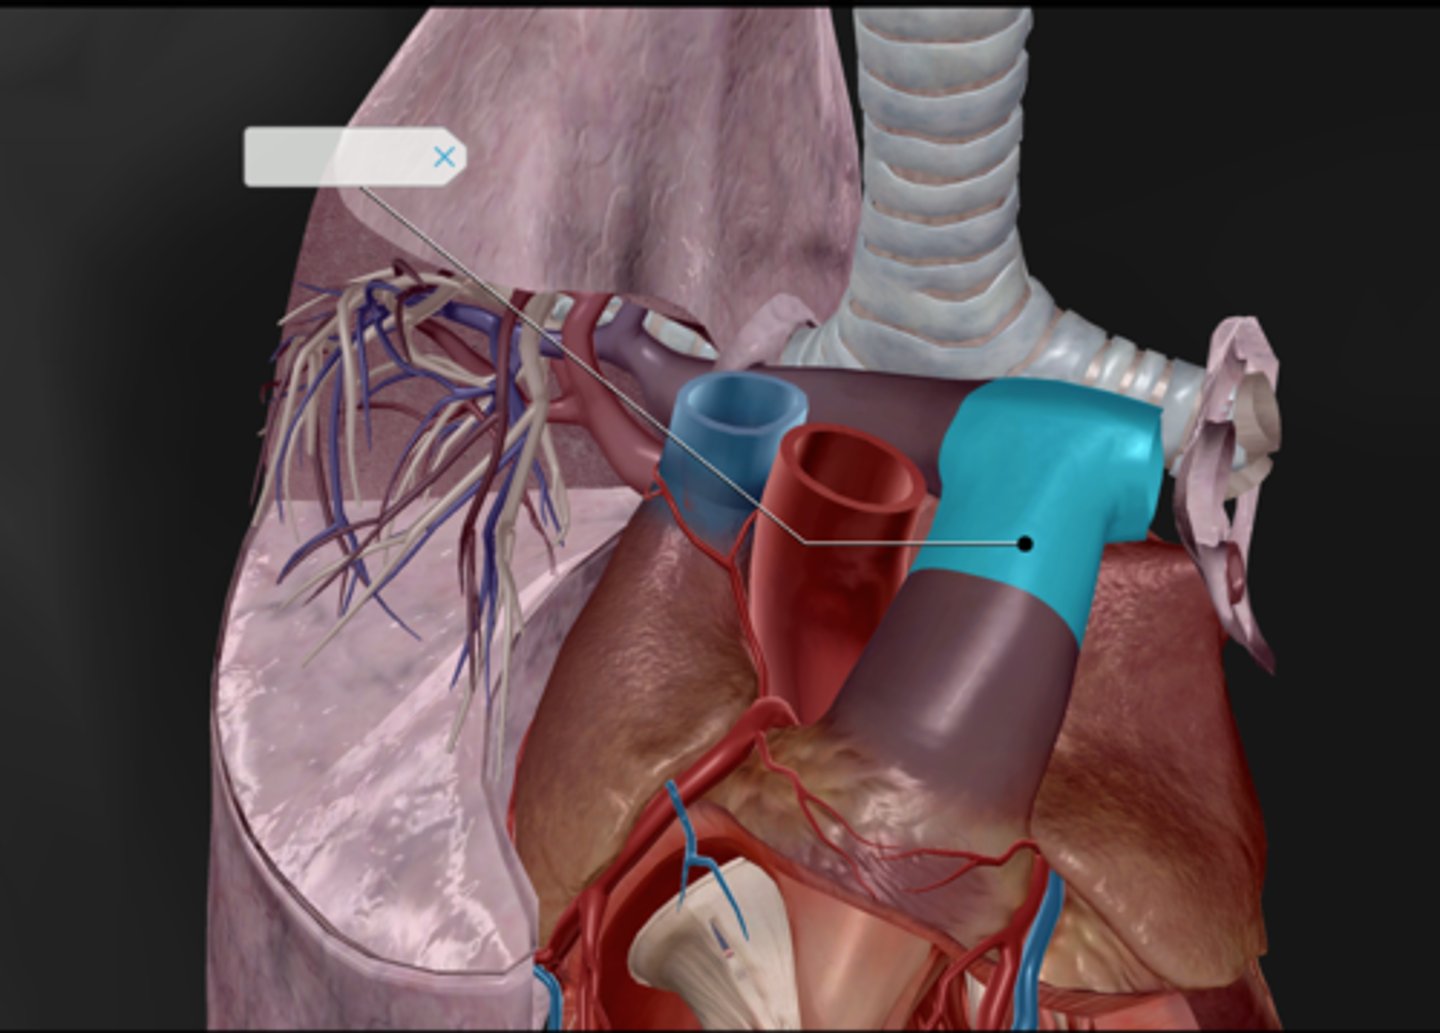

Pulmonary arteries

Pulmonary veins

Pulmonary trunk

Common carotid artery

Aortic arch